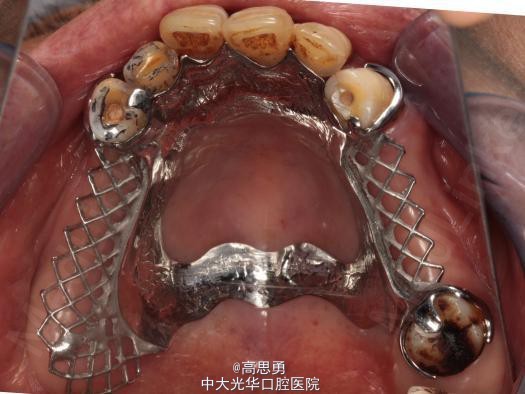

诊断: 1、牙列缺损(上颌肯氏II类I分类,下颌肯氏II类II分类) 2、#13慢性根尖周炎 3、#11、#12、#13、#21、#22、#23、#33、#42、#43、#44楔状缺损 4、慢性牙周炎 治疗计划 1、#13转牙体牙髓科做RCT 2、转牙体牙髓科对#11、#12、#13、#21、#22、#23、#33、#42、#43、#44楔状缺损 充填治疗 3、转牙周科进行牙周洁治 4、择期RPD修复 备选修复方案: 1、#13RCT后截冠后,上下颌覆盖义齿修复; 2、#13RCT后冠修复,上下颌可摘局部义齿修复; 3、#13RCT后树脂充填,上下颌可摘局部义齿修复; 4、#13拔除后,上下颌可摘局部义齿修复。 患者意愿:患者希望尽量保持#13的天然形态,要求费用尽量低,但能恢复正常咀嚼功能。 最终治疗方案:根据患者的年龄、身体状况、治疗周期、经济状况,患者最终选择方案5,即#13RCT后树脂充填,上颌结合卡环式可摘局部义齿修复;下颌可摘铸造支架式局部义齿修复。 治疗过程: 1、临床检查和#13树脂充填 对患者进行全面的口腔检查,用Z350树脂充填#13,调HE,抛光。 2、研究模型 调拌藻酸盐印模材料于2号成品托盘上取上下颌研究模,灌注石膏模型,研究分析、制定治疗计划,并制作个别托盘。 3、基牙预备 对#13近中、#23远中、#27近中、#34近中、#47近中常规制备支托凹,抛光。 4、工作模型 调拌藻酸盐印模材料于个别托盘上。做一定的边缘整塑,取上下颌研究模,灌注石膏模型。 5、试戴支架 检查支架的就位、固位可,无翘动,调HE,抛光,用蜡堤取颌位关系,上颌架,排牙,比色C4。 6、试排牙 检查义齿的就位、固位可,无翘动,观察人工牙的咬合状况,尖窝接触良好,正中颌位能重复,患者无诉不适,面容自然,外观满意。送加工厂充胶制作最终修复体。 7、试戴 检查义齿的就位、固位可,无翘动,咬合关系正确,利用咬合纸检查,上下颌尖窝接触均匀全面,抛光,患者表示满意,嘱注意事项,定期复诊。